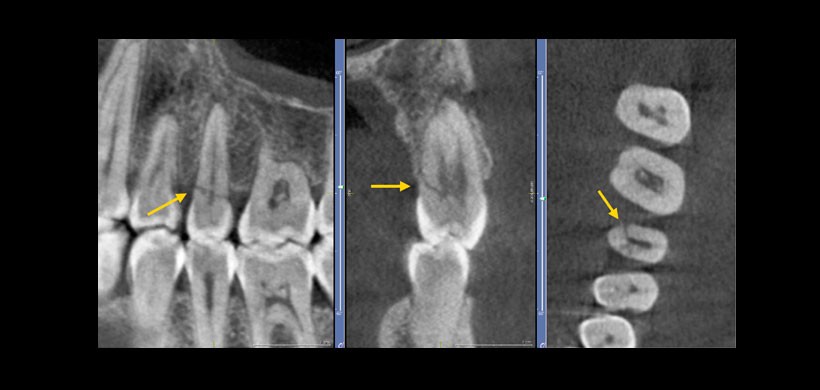

Fig 3. Tomografía computarizada de haz cónico. Vista Tangencial, transaxial y axial, se evidencia Fractura radicular visualizada en segundo premolar superior izquierdo.